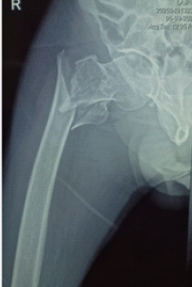

Intertrochanteric Femur Fracture in Severe Peripheral Vascular Disease Complicated by Acute Limb Ischemia and Amputation: A Case Report

Killi Madhu Babu , Sai Surya Dinesh Pydi , Vishal Kumar , Sandeep Patel

………………………………p.167-171